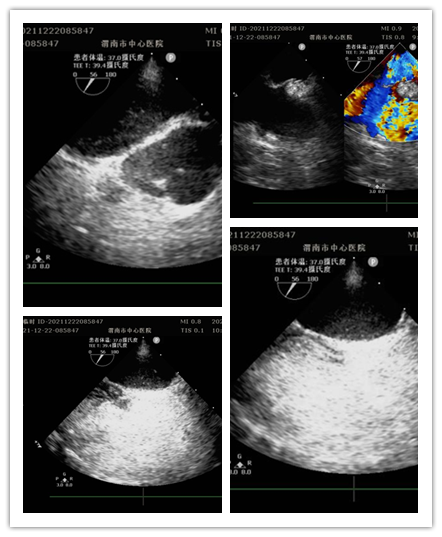

患者女性,13岁,因间断眩晕1年,加重伴头痛20余天就诊于医院全科医学科。住院期间,行经胸超声右心声学造影提示存在心内分流,为进一步明确心脏疾病,行经食管超声心动图检查。检查前,超声科杨玉萍医师对患者充分评估,与刘晓晖主任共同商定患者检查方案,进行充分准备。为保障小患者安全,全科医学科副主任医师苗娟妮、心脏外科副主任姜永红及团队全程参与。在多名医护人员的通力协作下,成功为患者行经食管超声检查。检查过程顺利,患者无不良反应,最终明确超声诊断,为患者进一步治疗提供了有力依据。

经食管超声心动图检查是将超声探头插入食管,直接贴在心脏的后方,从后向前观察心脏、血管和血流动力学情况,避免了气体及脂肪的干扰。加之食道超声的探头频率高于普通经胸超声探头,所以能扩大心脏的扫查范围,提高图像质量及细微分辨率。主要运用于术前评估、术中监测、术后复查,尤其是对经胸超声心动图检查成像困难或有关结构显示不清,致使诊断难以明确的各种心脏或大血管疾病患者,能更加准确地诊断心脏细小病变及疑难疾病。特别是能有效评估房颤患者血栓形成的危险性并作为可靠依据,对房颤治疗前期评估具有重要意义。